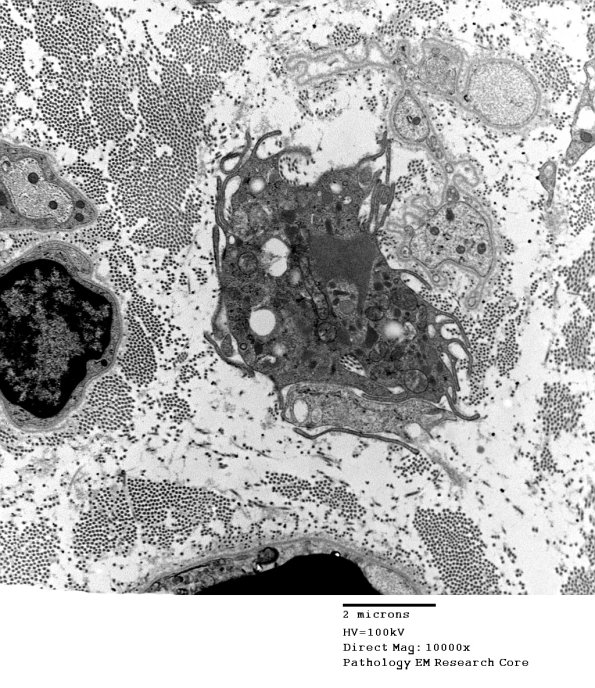

3H1,2 A macrophage leaving a group of Schwann cell processes which contain no myelin debris.